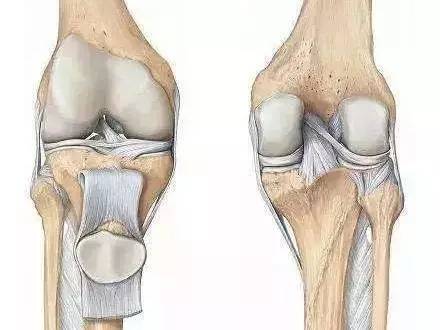

膝关节内侧疼痛的常见原因及处理方法

膝关节内侧疼痛的常见原因及处理方法

你好。从你说的目前情况来看。你的膝关节内侧有疼痛。上楼和蹲下盘腿时都会有疼痛加重的情况。像这种情况一般考虑,可能你的半月板有退变和损伤。建议你到医院做一个膝关节磁共振检查看看。

[最佳答案] 建议去医院检查一下 看是不是内侧半月板有破裂或是内侧韧带有严重的拉伤 膝关节周围的韧带多 力量大 伤了后 容易引起强烈的痛感 也不容易好 所以 你现在不要再做

膝关节是人体最大、最复杂的关节,也是跑步中伤病出现最繁多的部位。单是膝内侧疼痛就包括了内侧副韧带损伤、鹅足肌腱损伤、内侧半月板损伤

[最佳答案] injury”过度使用伤,其发生原因与高频次的屈伸膝关节、内收内旋小腿高度相关,所以鹅足腱滑囊炎在跑者当中并不少见。 二、膝内侧痛主要症状1. 膝关节前内侧疼